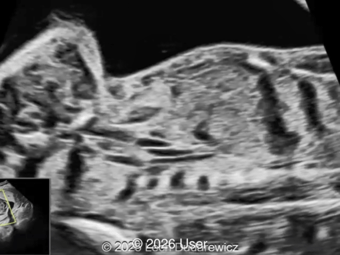

A 26-year-old primigravida with no significant past medical or family history was admitted at 18 weeks of gestation with preterm premature rupture of membranes. At 20 weeks of gestation, a detailed fetal ultrasound was performed under conditions of severe oligohydramnios, followed by fetal magnetic resonance imaging (MRI). Non-invasive prenatal testing (NIPT) for common aneuploidies was negative.